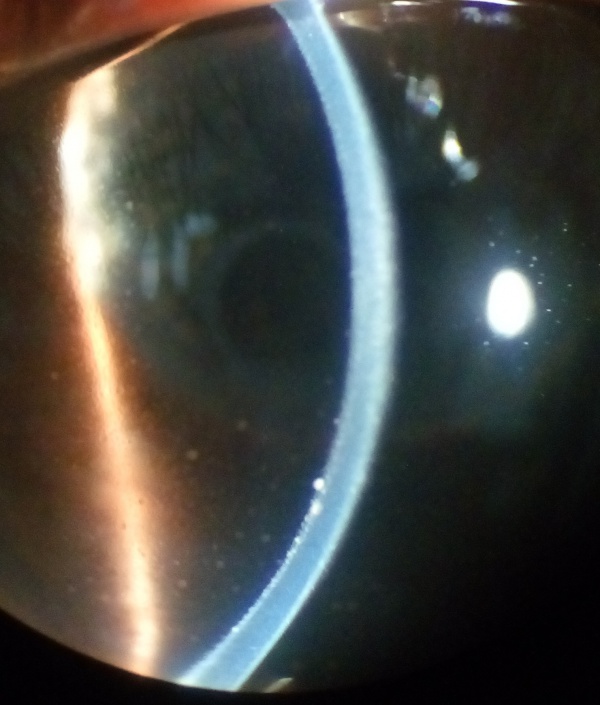

The chronic or convalescent stage will take place weeks after the uveitic stage. It is characterized by the development of vitiligo, poliosis, and depigmentation of the choroid.[11] Sugiura sign (perilimbal vitiligo) is the earliest depigmentation to occur,[13] presenting itself 1 month after the uveitic stage.[6] Choroidal depigmentation occurs several months after the uveitic stage, leading to a pale disc with a bright red-orange choroid known as a “sunset-glow fundus.” This phase may last several months.[11]

- Ocular depigmentation (either of the following manifestations is sufficient): Sunset glow fundus, or Sugiura sign.